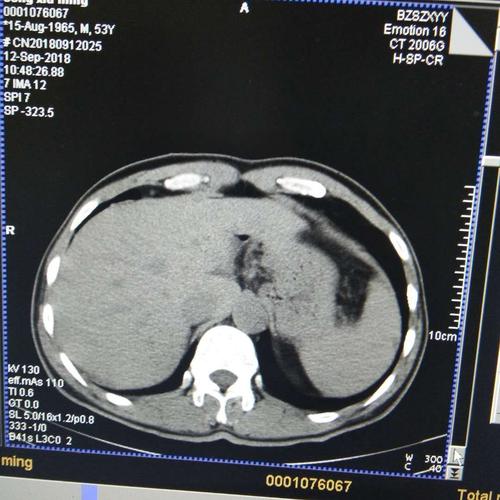

肝囊肿ct图片报告,肝囊肿ct图片

肝囊肿-腹部ct诊断-医学

肝囊肿ct图片

肝囊肿ct图片影像

肝囊肿ct图片怎么看

多发性肝囊肿ct图片

肝囊肿ct